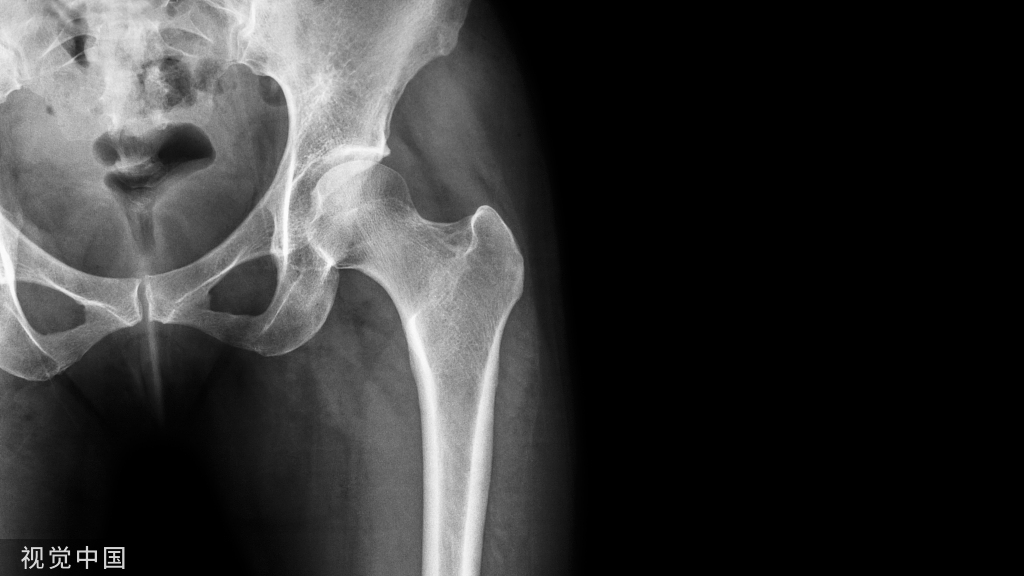

创伤性踝关节骨性关节炎前侧锁定钢板内固定踝关节融合手术前后X线片

1、前侧入路

前侧入路是以踝关节间隙为中心作前方纵形切口,逐层切开,沿肌腱间隙进入;切开关节囊,显露胫距关节,去除软骨及软骨下骨,将前侧钢板置于踝关节前方。

2、外侧入路

外侧入路是于腓骨尖上约 10 cm 处截骨并将残端完全剥离取出,取残端松质骨待植骨用,完成融合面截骨并冲洗,将钢板贴伏踝关节外侧。

优点在于固定强度较大、固定牢靠,可用于踝关节严重内翻或外翻畸形、清理后存在较多骨缺损病例的修复和重建,通过解剖设计的融合钢板有助于恢复踝关节正常的解剖位置。

缺点在于需要较多地剥离骨膜及术区软组织,且钢板较厚,容易对周围肌腱产生激惹,置于前方的钢板容易在皮下触及,存在一定风险。